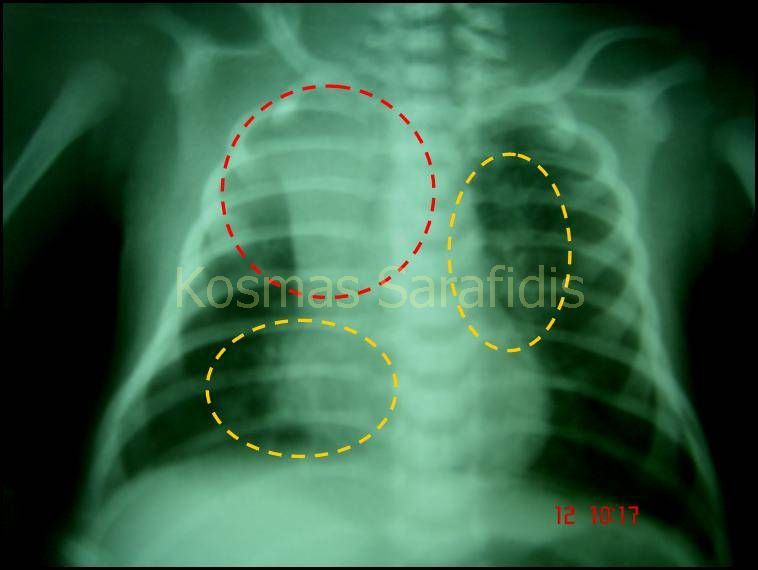

Σωστά. Στην ακτινογραφία θώρακα φαίνονται διάσπαρτες αμφοτερόπλευρες διηθήσεις, περιβρογχική πάχυνση και ατελεκτασία του δεξιού άνω λοβού. Στο αριστερό κάτω πνευμονικό πεδίο διακρίνεται τοπικά υπεραερισμός. Το μέγεθος της καρδίας είναι φυσιολογικό.